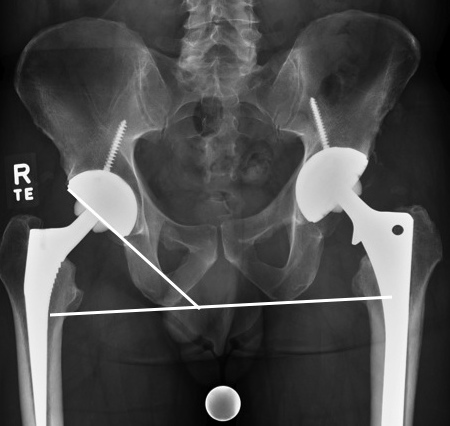

DEFINITION:

Angle formed between slope of cup and line drawn through base of ischial tuberosities (RID2550 ) -- or teardrop

ABNORMAL:

if < 30 degrees then reduced abduction

if > 50 degrees then increased dislocation

how to draw the angle of inclination